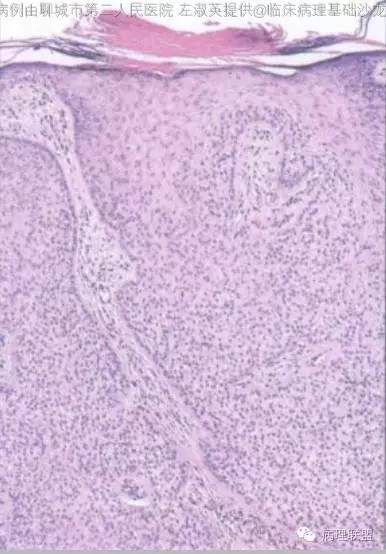

部位表浅,境界较为清楚,伴有不全角化;病变与表皮相连,由浅染细胞构成,周边细胞栅栏状排列;毛囊周边上皮环抱状改变;细胞无异型,核分裂看不太清(就知道这么一丢丢)@左淑英

@刘香丽 后面会有总结的,先看看书,记忆更好,外毛根鞘瘤:低倍看内生性生长,淡染或透明的鳞状细胞构成,边缘栅栏状排列的基地样细胞,外有嗜伊红地基底膜样物质。